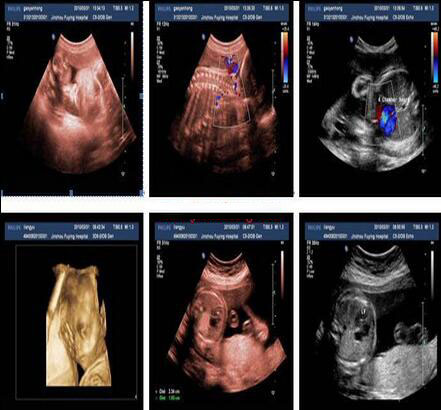

君安康公司的新型环保医用胶片优势:高清、打印速度快、不怕曝光、无毒、多用途,价格低廉。B超胶片:适用于超声、病理、胃肠镜检查室等。B超胶片:适用于超声、病理、胃肠镜检查室等。规格:A4(210*297mm),16K(210*285mm),B5(182*257mm) 更多 超声PACS医用诊断报告胶片 价格、说明、厂家,请关注医贸天下医疗器械网